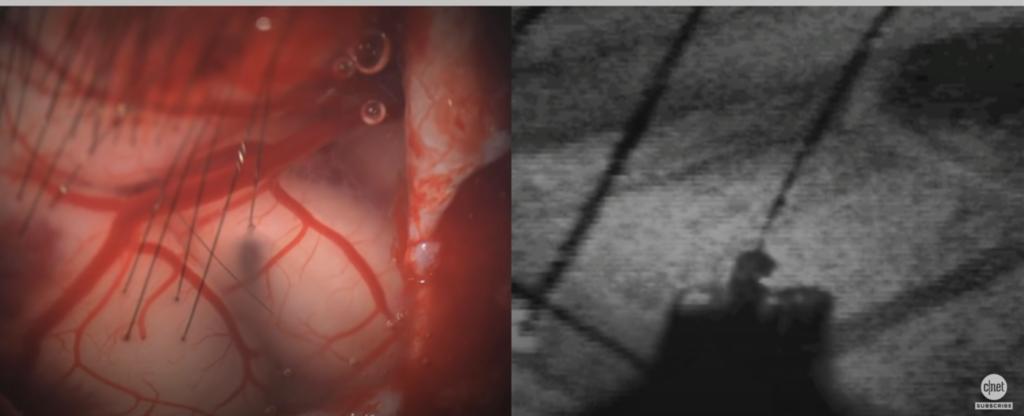

首先从大脑顶上先扒开皮,然后把头盖骨切出一个一块钱硬币那么大的洞,把Neuralink放进去,把1024根电极插入脑皮层灰质。更为难得的是说,整个手术大部分是机器人可以完成的,名副其实的大开脑洞。好在只用开一次,之后是可以每天无线充电,无线蓝牙传输信号的。

第一只是正常小猪,第二只是植入Neuralink又摘除的小猪,都还活蹦乱跳。最关键的是第三只小母猪,名叫Gertrude,展示现场就是植入的状态,运动和吃东西时候,会兴奋的哼哼,同时显示脑电波有明显波动。